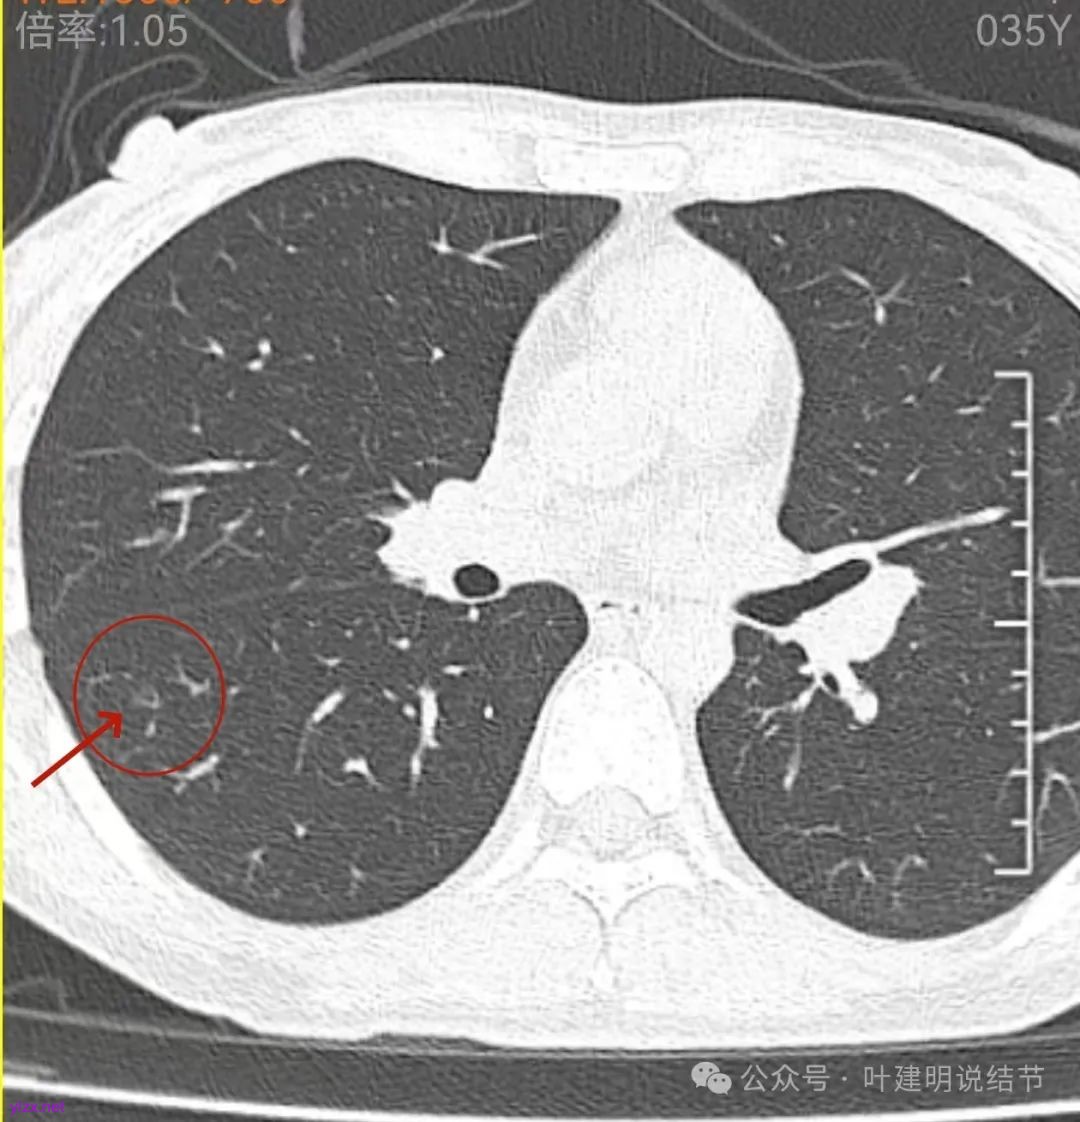

表面不平,轮廓较清,有血管进入,边缘略显毛糙。

病灶内有少许偏实性成分,与血管关系较为密切,局部似有浅分叶的样子。

这层面看,密度不纯,部分区域的边缘有细毛刺征。但感觉与前一层面的结节形态不似延续过来的。

边缘区密度也略显高,圆形的样子。

两肺多发结节,左侧黄色标注的考虑是肺泡上皮增生可能性大;蓝色的考虑肺泡上皮增生或者少许慢性炎可能性大;右侧红色宽起来并带有红色箭头的这处是主病灶,偏混合密度,整体轮廓较为清楚,边缘显得毛糙,从2024年12月份的来看,要考虑是肿瘤范畴,原位癌或者微浸润性腺癌可能性较大,也不能完全排除不典型增生。但是在2022年的时候,这个病灶的边上也有一个实性的微小结节,如果只看2022年的,这么小的实性结节,又比较圆,表面也显得较为光滑,是要考虑良性的,当然太小了需要动态观察。回头再重新来看2024年底的,发现绿色箭头所指的这个微小实性的较2022年几乎没有变,去仔细寻找2022年的,发现当时在实性结节旁边也有密度很淡的一点磨玻璃影(也可能真的就是一处,只是扫描不够薄,密度的变化有些突兀而已),而到了2024年12月份,实性微小这处没有明显变化,但是原来很淡的磨玻璃变成了混合磨玻璃,范围也明显扩大。所以总体来看右肺下叶这处是考虑恶性的,而且从磨玻璃结节角度来讲,还是生长比较快的,就是说还是有一定风险的。加上左侧还有两处也是磨玻璃持续存在,虽然边缘轮廓显模糊一点,但多年以后也可能仍然要变成原位癌或者微浸润性腺癌之类的东西。通盘考虑以后,我倾向于右侧近期单孔胸腔镜下微创局部切除,左侧随访观察,等到有进展并风险增加再来考虑处理。意见供参考!